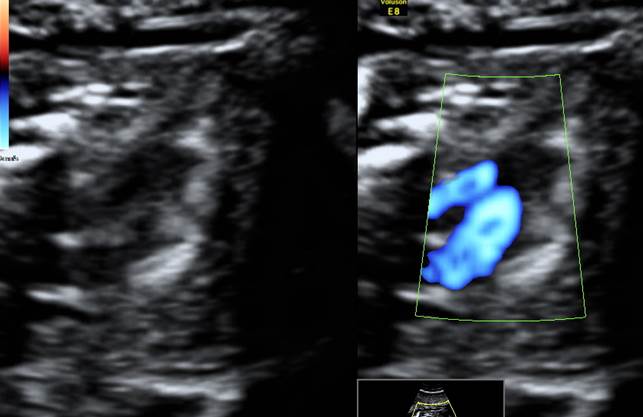

Монохориальная двойня. Какой ВПС у обоих плодов?

- У обоих плодов из МХ двойни есть один из самых частых и маркерных для трисомии 21 ВПС — атриовентрикулярный канал АВК

- Причем заметьте, в этом случае он прекрасно виден как в апикальной (у 2 плода), так и в базальной (у 1 плода) позиции сердца

- Была проведена аспирация ворсин хориона, диагноз — трисомия 21